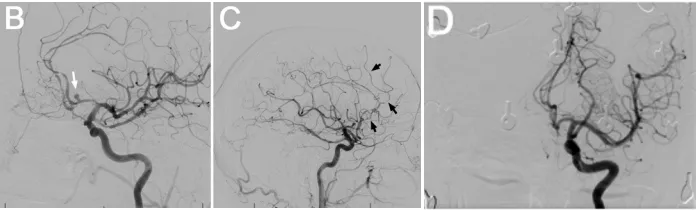

患者神志清醒,对答切题,但存在左侧轻偏瘫及共济失调。数字减影血管造影(DSA)显示,A1-A2复合体近端及前交通动脉瘤周围存在显著的放射性血管炎(图1B-D)。

B:DSA侧位像显示动脉瘤(箭头)。C:DSA侧位像显示放射性血管炎,表现为血管分支减少及多处血管狭窄(箭头)。D:DSA正位像显示2年前Wada试验时未见动脉瘤或血管炎性改变。

血管造影亦证实存在放射性血管炎。患者随后接受经右侧额部翼点入路开颅术行动脉瘤夹闭术,手术过程顺利。术后DSA显示动脉瘤闭塞有效,无并发症(图1E-G)。